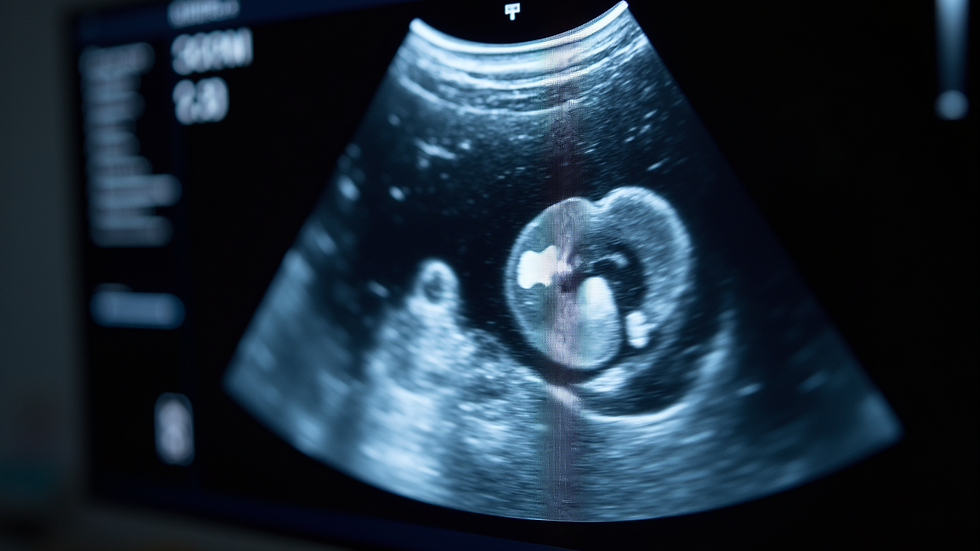

Ultrasound merupakan metode diagnostik yang sangat penting untuk memeriksa kesehatan kucing, terkhusus saat ada indikasi masalah di kandung kemih. Sebagai pemilik kucing, penting untuk memahami hasil ultrasound agar Anda dapat mengambil langkah perawatan yang tepat. Artikel ini akan membahas cara membaca hasil ultrasound dan cara membedakan antara tumor dan sedimen atau batu.

Ultrasound adalah teknik pencitraan yang memanfaatkan gelombang suara untuk menghasilkan gambar organ dalam. Prosedur ini non-invasif dan biasanya dilakukan di klinik hewan. Dalam kasus kucing, ultrasound sering ditujukan untuk mengevaluasi kesehatan kandung kemih, ginjal, dan organ lainnya. Data yang dihasilkan dapat membantu dalam mendeteksi berbagai kelainan.

Hasil ultrasound membawa informasi vital mengenai kesehatan kucing Anda, tetapi bisa membingungkan. Oleh karena itu, diperlukan pengetahuan untuk memahami apa yang ditampilkan dan bagaimana membedakan tumor dari sedimen atau batu.